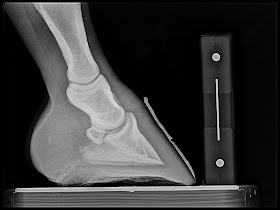

First case is a chronic navicular with rotational and varus limb deformities. Goal is to increase tendon surface angle, Palmar angle and reduce digital breakover.

Below: Quarter race horse that goes off after 150 yards or so and quits running. 4yrs old and has moderate navicular changes already. Placed in Rockered Race shoe from NANRIC to increase TSA and PA. This will unload DDF/nav bone engagement and small osteophyte at dorsal aspect of coffing joint.